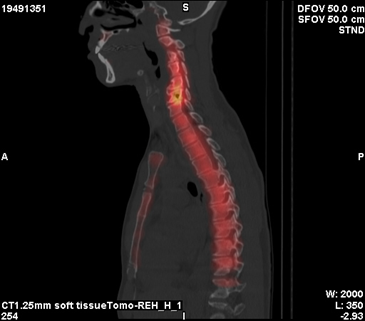

Clinical examination revealed tenderness confined to the neck and upper back, as well as tenderness in the lower back and sacroiliac joints. Cervical rightward rotation and left shoulder elevation were restricted. Laboratory tests showed a mildly elevated eosinophil count (8.0%). Imaging studies, including cervical spine AP and lateral X-rays, demonstrated C5-C7 intervertebral space narrowing and retrolisthesis. Tc-99m methylene disphosphonate (MDP) whole body bone scan with whole-body imaging was arranged, and localized imaging with single-photon emission computed tomography (SPECT)-CT for cervical-thoracic spines confirmed increased radiotracer uptake in the C6 vertebra, identifying a 0.7 cm cystic lesion (Figure 1). On T1-weighted images, the intervertebral disc was clearly seen herniating into the C6 vertebra, with the herniated portion connecting to the cavitated lesion (Figure 2A). Another image (Figure 2B) demonstrated the C7 vertebra compressing the intervertebral disc upward, causing partial rupture. On T2-weighted images, the cavity appeared hypointense (Figure 3A & 3B), and a distinct ring of sclerosis surrounds the cavity (Figure 3B), which is characteristic of Schmorl's cyst.4 Based on axial images (Figure 3C), it is suggested possible prior communication with cerebrospinal fluid. Furthermore, degenerative disc disease (DDD) was noted at C3-C4 and C4-C5, while C5-C6 and C6-C7 showed DDD with grade I retrolisthesis.

Figure 2 On T1-weighted images, the intervertebral disc was clearly seen herniating into the C6 vertebra, with the herniated portion connecting to the cavitated lesion (Figure 2A). Another image (Figure 2B) demonstrated the C7 vertebra compressing the intervertebral disc upward, causing partial rupture.

In view of radiologic evaluation, proper image provided critical insights into the pathology. X-ray imaging revealed that the vertebral contour remained intact, with no evidence of aggressive bone destruction (not shown). On the bone scan, there was increased radiotracer uptake in the C6 vertebra (Figure 1), consistent with the first scintigraphic findings in Schmorl’s node.5 MRI images showed the intervertebral disc herniating into the C6 vertebra, with the herniated portion connecting to the cavitated lesion (Figure 2A & 2B), and the C7 vertebra compressing the intervertebral disc upward, causing partial rupture. Also, the cavity of C6 appeared hypointense (Figure 3A & 3B), with a distinct ring of sclerosis surrounds the cavity (Figure 3B), which is characteristic of Schmorl's cyst.4 MRI findings further clarified the pathology of Schmorl’s node, which typically appears a small bony notch filled with herniated disc material in the upper or lower endplate of a vertebral body.6